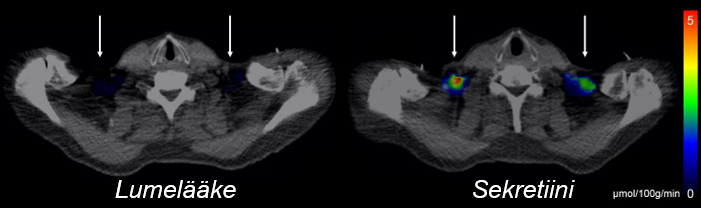

PET-kuva glukoosimerkkiaineen soluunotosta lumelääkkeen ja sekretiinin annostelun jälkeen.

Positroniemissiotomografiakuva glukoosimerkkiaineen soluunotosta lumelääkkeen ja sekretiinin annostelun jälkeen. Nuolet osoittavat ruskean rasvakudoksen alueen.